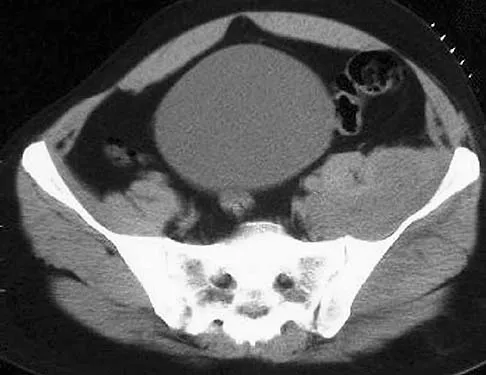

A 40-year-old laborer sustains the injury shown in the radiograph and CT scan in Figures 56a and 56b. What is the most common complication associated with surgical intervention?

Explanation